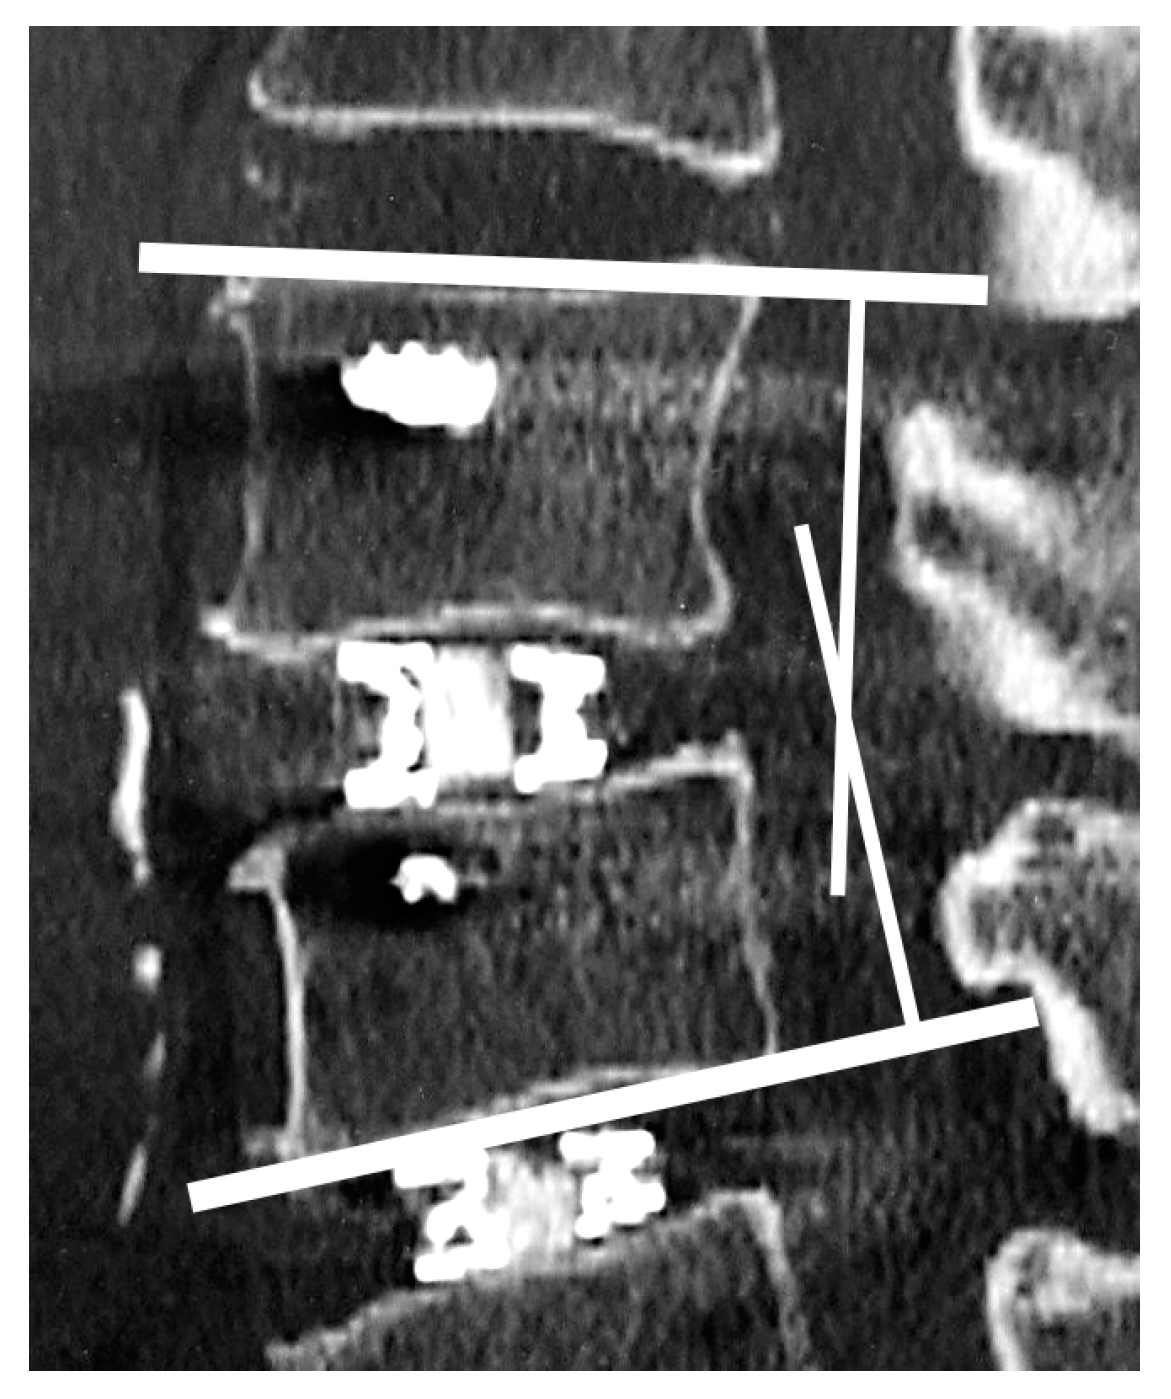

2.4. Radiological Assessments

2.5. Vertebral Endplate Concavity (VEC) and Cage Subsidence